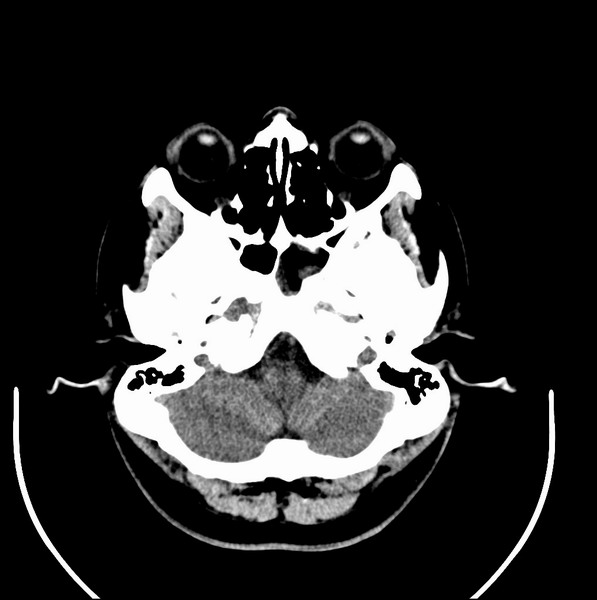

男、30、发现鼻咽部肿瘤侵犯海绵窦,未发现明显淋巴肿。请问国内那家医院治疗鼻咽部肿瘤最好?手术以何种方式为主?病灶可否全部切除?急切期待的大家的帮助。

扫描示鼻咽腔不对称,中度狭窄,右侧咽隐窝消失,局部软组织肿块,鼻咽右侧壁增厚形成肿块,突入鼻咽腔,肿块平扫呈等密度,肿块向深部侵润,右侧翼内外肌受侵,右侧咽旁间隙变窄;向后生长,头长肌界线欠清,向后上生长侵犯同侧颈动脉鞘区。双侧海绵窦增宽,内见软组织影与鼻咽部肿块相连。考虑鼻咽癌。鼻咽癌主要是放射治疗,且效果较好;到当地有治疗设备较大医院治疗即可。